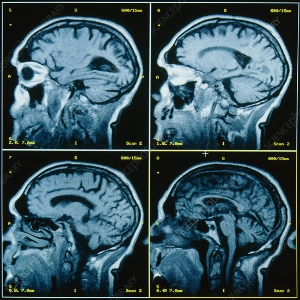

brain scanPTA is a condition that follows a traumatic blow to the head. After my ten days of an induced coma, my brain was a little shaken. I had trouble comprehending where I was. Yes, apparently I had crashed my paraglider while taking someone for a joy flight, which I still have no memory of. It is a very confusing state in which your “self” and your consciousness gradually reform.